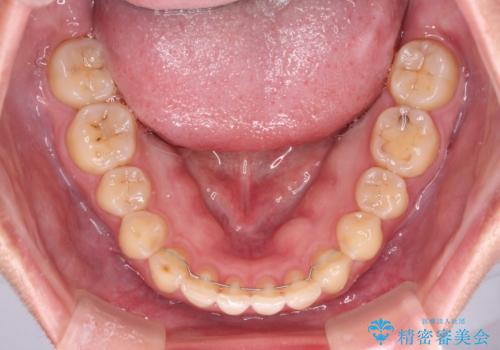

- 食いしばりが気になっていたとのことで来院された患者様です。

当初は睡眠時のマウスピースのみの製作をご希望でしたが、矯正治療の提案をしたところ、インビザラインにて矯正治療を行うこととなりました。

矯正治療中に食いしばりがより強くなることがあるため、半年に1回のペースでボツリヌストキシンによる咬合力緩和を並行して行うこととしました。

咬合力の緩和と食いしばりがちな咬み合わせが改善され、顎の負担が大幅に軽減されました。